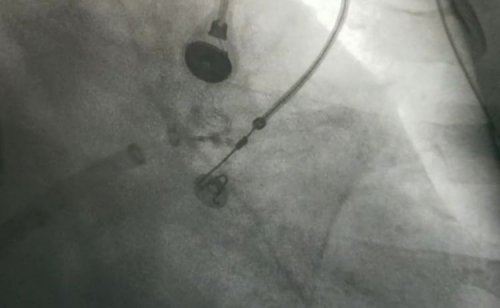

手术中,房颤消融环肺静脉完全隔离,左心耳完全封堵,手术用时仅花费3个小时,封堵和消融效果都非常完美。术后第二天徐阿姨便能下床活动,活动后无不适,并且无任何手术并发症,患者可以顺利在45天后就改变用药方案,不必再担心抗凝中断的风险。